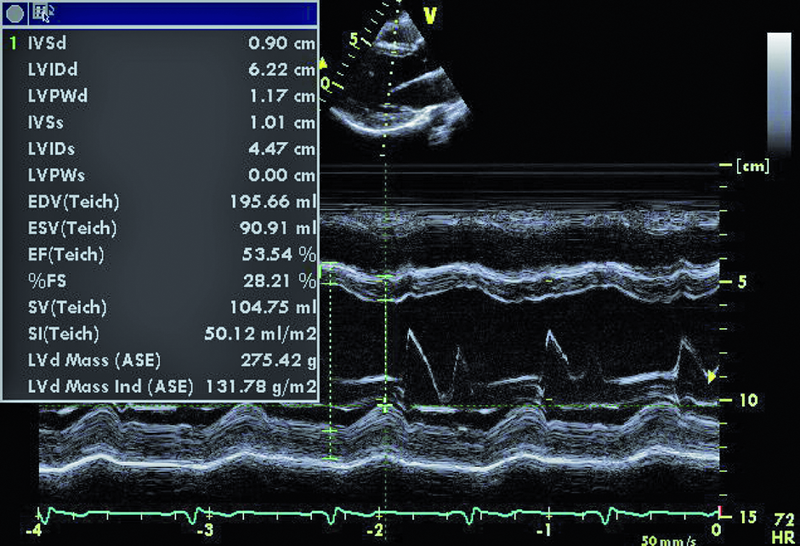

Mężczyzna, lat 28, pozostawał w dzieciństwie pod opieką kardiologów z powodu wrodzonej wady serca. Przeprowadzono wówczas pełną diagnostykę z cewnikowaniem serca i ustalono rozpoznanie. Rodzice chłopca nie wyrażali jednak zgody na leczenie operacyjne. Pacjent przez wiele lat nie miał objawów. W 2007 r., już jako dorosły mężczyzna, przebył infekcyjne zapalenie wsierdzia leczone farmakologicznie z dobrym skutkiem. Chory przyznał w czasie konsultacji, że przed przyjęciem na oddział wad wrodzonych serca u dorosłych od roku odczuwał dyskomfort w klatce piersiowej. Objaw występował zarówno w spoczynku, jak i w warunkach obciążenia. Nie przyjmował leków. Nie zauważył upośledzenia tolerancji wysiłku. W badaniu przedmiotowym zwrócono uwagę na szmer ciągły w trzeciej przestrzeni międzyżebrowej po stronie lewej. W EKG rejestrowano rytm zatokowy, bez zmian w zapisie. W badaniu echokardiograficznym stwierdzono m.in. niedomykalność płucną o niewielkim stopniu zaawansowania z prawidłową wielkością jam prawego serca. Powiększona natomiast była jama lewej komory (62 mm), a jej kurczliwość oceniono na nieznacznie upośledzoną (EF 54%). Rejestrowano małą niedomykalność aortalną i mitralną.

W badaniu echokardiograficznym zwrócono uwagę na powiększenie jamy lewej komory z nieznacznie upośledzoną kurczliwością mięśnia (ryc. 1). Stwierdzono także trójpłatkową zastawkę aortalną (ryc. 2) ze śladową niedomykalnością oraz małą niedomykalność mitralną. Te nieprawidłowości nie mogły tłumaczyć szmeru ciągłego w badaniu fizykalnym ani też nieznacznie powiększonej sylwetki serca. Przyczyną szmeru ciągłego jest najczęściej przetrwały przewód tętniczy Botalla, łączący aortę i pień płucny. Połączenia takiego jednak w miejscu typowym nie znaleziono. Rejestrowano u chorego prawidłową średnicę pnia płucnego (ryc. 3) oraz nieznacznie przyspieszoną prędkość wypływu płucnego (ryc. 4). Szmer ciągły nakazywał poszukiwać innych rzadkich połączeń między dużymi naczyniami. Jedną z nich jest okienko aortalno-płucne, czyli tzw. fenestracja aortalno-płucna, i tę wadę właśnie rozpoznano u chorego.